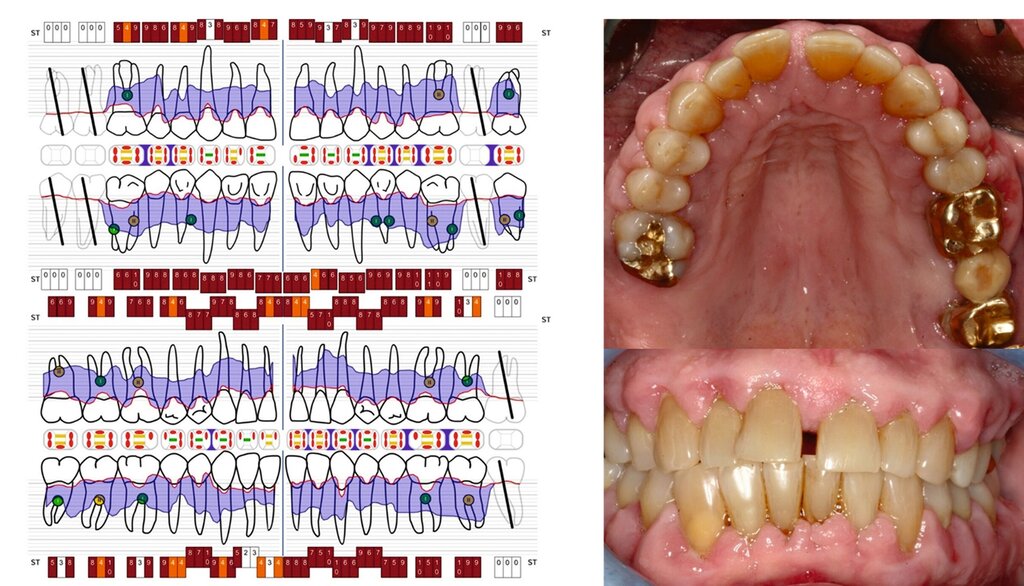

Dennoch geben Prognosesysteme, insbesondere bei komplexen Situationen, eine Hilfestellung bei der Entscheidung über den Zahnerhalt. Jedoch sollte man diese zu unterschiedlichen Zeitpunkten innerhalb der Parodontitistherapie erneut durchführen und sich wiederholt die Frage stellen, ob durch die derzeitige Therapie eine parodontale Stabilität des Zahnes erreicht werden kann [Kwok und Caton, 2007]. Die Abbildungen 5 bis 8 stellen diese Situation bei einem 56-jährigen Patienten mit Parodontitis dar, bei dem sich die zahnbezogenen Prognosen nach drei Jahren Parodontitistherapie deutlich verbessert haben.